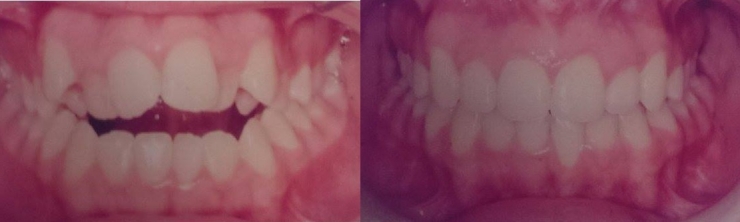

Because her jaw was misshapen, her teeth were not aligned well, and so she had to wear braces. She was insulted by regularly being called a 'monster'. She explains that some other students' parents even looked at her with disgust!

And indeed, with time after surgery, the transformation is impressive.